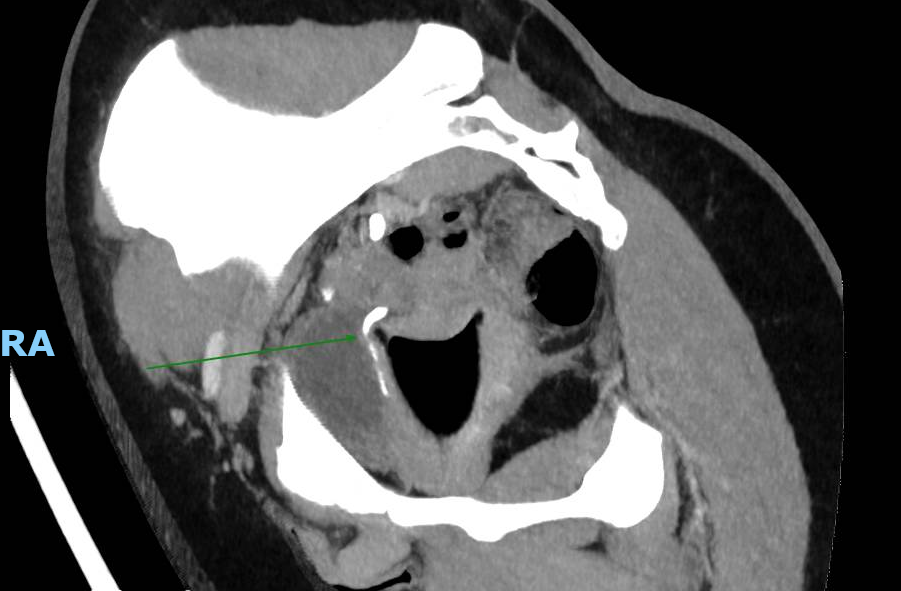

Le CT-scanner réalisé devant une colique néphrétique montre une compression urétérale droite extrinsèque sur une cup menstruelle. Cette dernière est retirée améliorant rapidement les douleurs.

Ce cas et la littérature qui y est liée démontre l’importance d’exclure la présence d’une cup en cas de colique néphrétique chez les femmes pré-ménopausées.